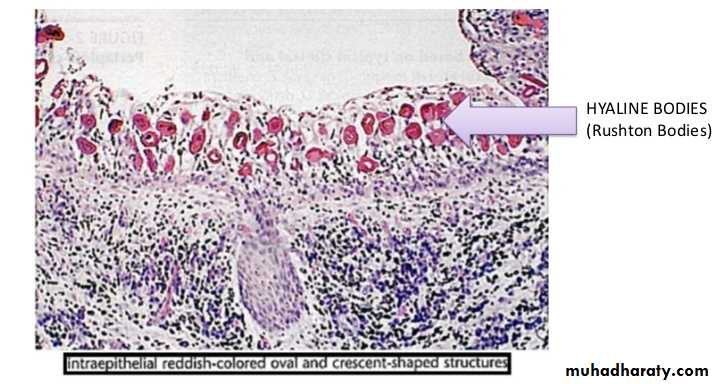

Histological Features.The epithelium lining the apical periodontal cyst is usually stratified squamous in type .

The usual squamous epithelium seldom exhibits keratin formation.

This lining epithelium varies remarkably in thickness.

During active growth the capsule is vascular and infiltrated by chronic inflammatory cells adjacent to the proliferating epithelium.

Hyaline bodies may be seen in the epithelium and mucous cells are often present as a result of metaplasia.

Long-standing cysts typically have a thin flattened epithelial lining, a thick fibrous wall and minimal inflammatory infiltrate.

The capsule consists of collagenous fibrous connective tissue.